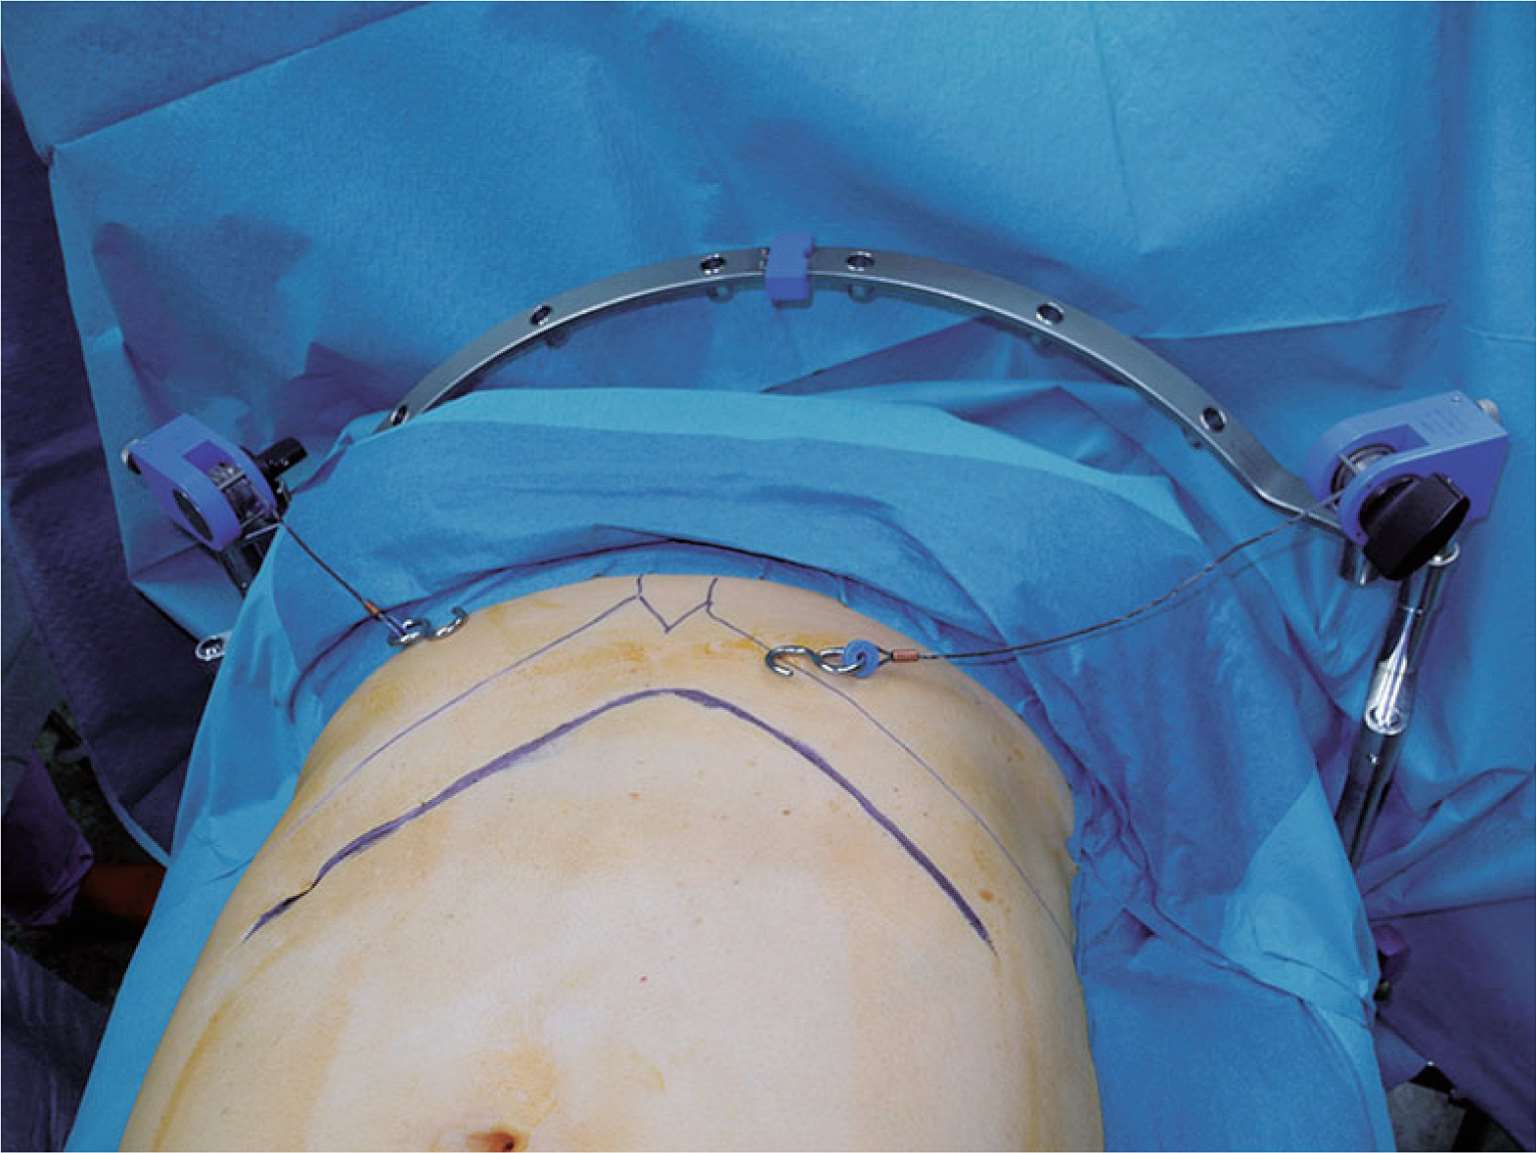

图2-4 身体矮胖或食管贲门肿瘤患者应行双侧肋缘下斜切口,以更好地显露术野。